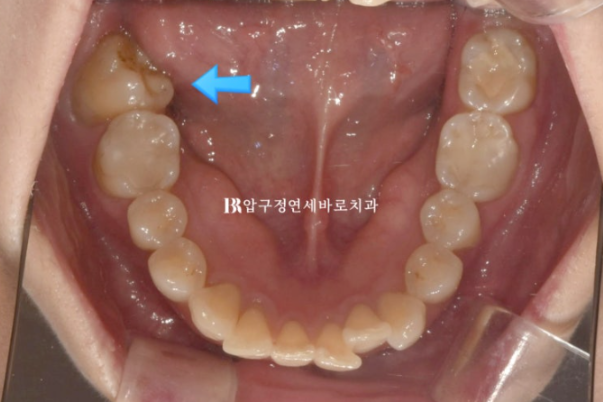

파란화살표 맨 뒤 큰어금니는 위 아래가 엇갈려 물리는 가위교합 입니다.

24.02

혀쪽으로 쓰러진 두번째 큰 어금니가 보입니다.

이 때문에 대합치인 위 두번째 큰 어금니와 제대로 교합이 안 되어서 가위교합 상태입니다.

이렇게 엇갈려서 교합이 안되는 상태를 가위교합 이라고 합니다.